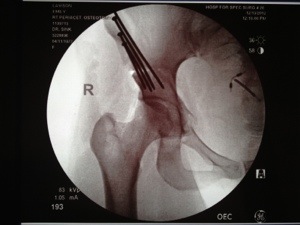

It looks like i will be released tomorrow to recuperate at home for several months. Dressing over the incision comes off tomorrow too! For the meantime, here is an x-ray of my right hip post-PAO (the doctor takes numerous X-rays during the procedure to be sure that the placement is correct and he kindly gave me a copy). More photos coming soon!